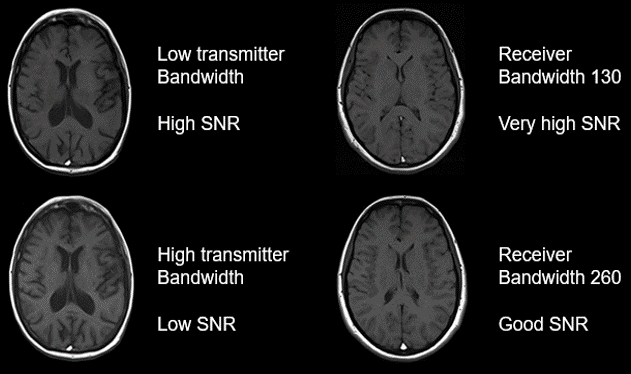

Bandwidth:

In MRI the bandwidth is the number of frequencies that are either transmitted or received in a period. The transmit bandwidth is the width of the transmitted. It is usually more narrow than the receive bandwidth to ensure the signal does not spread beyond the receive bandwidth.

Think of x-ray and beam collimation. More narrow beam collimation provides that the radiograph would have better detail, whereas a beam that is not collimated leads to scattering which appears as noise or quantum mottle on the radiography. Therefore, narrow or low transmit bandwidth results in higher SNR. The receive bandwidth is the opposite. Because the receive bandwidth represents the number of frequencies measured, a narrow receiver bandwidth will result in a higher SNR.